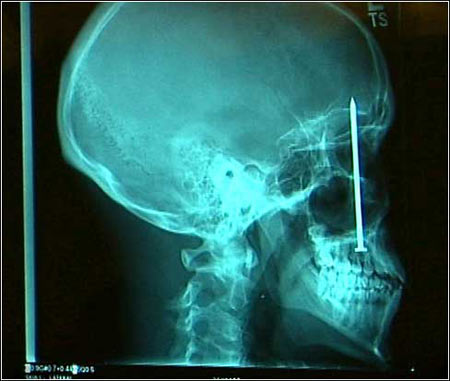

2005年度最佳照片----幅幅经典